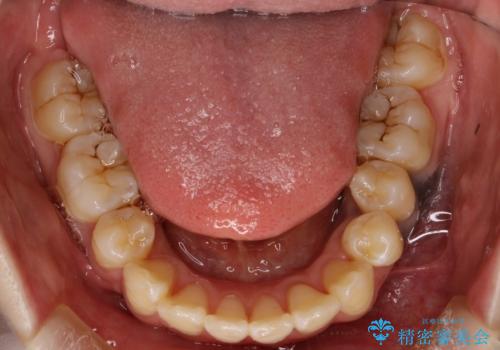

抜歯したスペースを使うことで、ガタガタと出っ歯を改善することができました。

- 矯正治療後の保定が不十分だと後戻り(元の位置に戻ろうとする動き)をします